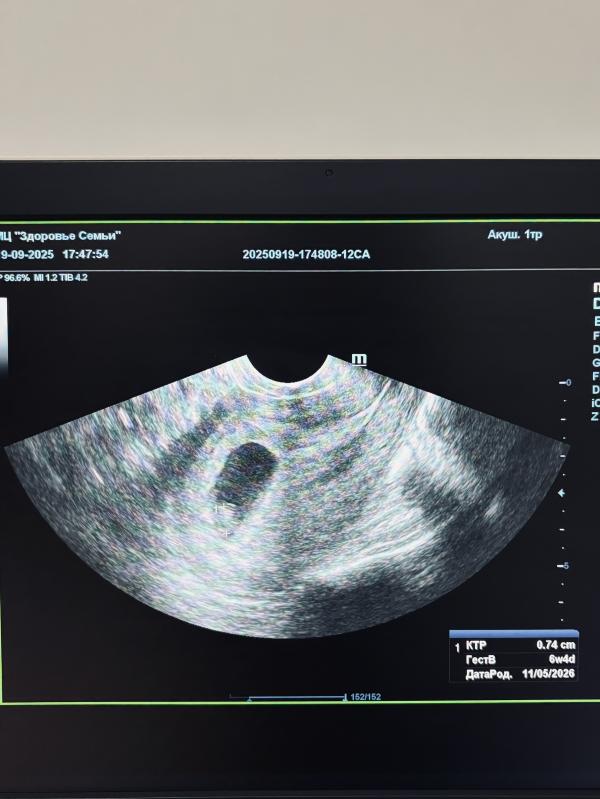

Потому что на узи я услышала: у Вас тут развивающаяся беременность, сердцебиение присутствует, сроку по мес соответствует 😭💔

Узистка, кстати, попалась крутая, гинеколог, несколько раз все проверила и успокоила.